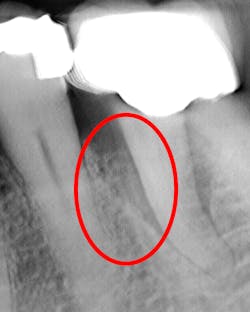

What’s unique about this system is that it uses nanotube technology to capture standard 2D images (figure 2) and gives you the option of taking a tomosynthesis image, which captures multiple images from several angles (figure 3). Images are compiled into a sliced volume and dissected into 0.5 mm or 0.1 mm slices that you can scroll through, rotate, enlarge, measure, and adjust. The system can “un-overlap” many teeth; this is convenient because with regular 2D x-rays, I had to retake the image at different angles and often with little success.

I see more complications and pathologies when using 3D tomosynthesis than I ever did with my old 2D images (figure 4). I can treat more because I can see more bone loss, interproximal caries, fractures, resorptions, abscesses, and more (figure 5).

In fact, twice today I was able to see something with Portray that wasn’t visible in the original 2D x-ray (figure 6). I don’t always take 2D images now, but I do when I think the case is straightforward or the patient has very little dental history. I often end up taking a tomosynthesis image just to be safe. With the 3D image I can scroll from buccal to lingual through the tooth and get much more data (figure 7). The new system has replaced my 2D PAs and bitewings.